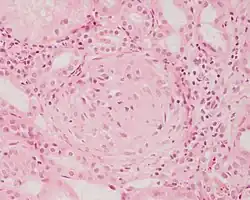

![]() | Meningoma | Concentrically calcified basophilic structure in the centre of the field in a meningioma. | Category: Histopathology of meningoma | meningoma |